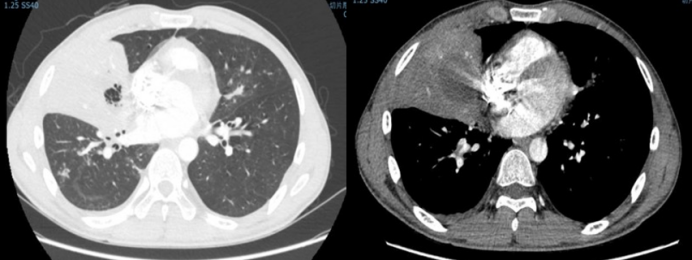

病例8:男性,51岁,主诉“反复咳嗽、咳痰4月余,间断发热1个月”于2021年12月27日入院。4个月前患者因急性淋巴细胞白血病就诊于某三甲医院行VICLD方案化疗,化疗期间出现咳嗽、咳痰伴间断发热,诊断为肺部感染。胸部CT提示肺部感染,查痰NGS提示小孢根霉;痰培养结果为耐碳青霉烯类鲍曼不动杆菌(CRAB),予抗感染及小剂量激素治疗后体温正常,咳嗽、咳痰好转。既往史:患者于2020年6月确诊为急性B淋巴细胞白血病,2020年7-9月分别行VDLD、CLEA、HD-MTX/VL化疗3次,2021年7月白血病复发。2021年12月28日入院后胸部CT示:左下肺病变严重,增强CT检查在此发挥重要作用,可辅助评估病灶出血风险及制定规避出血的策略。支气管镜检查(图15)及组织病理学(图16)均提示毛霉感染,mNGS进一步明确诊断。由于患者血小板水平极低,一般状况差,无法耐受外科手术,遂采用支气管镜介入清创术(图17)。术中取出的由大量毛霉菌丝杂乱缠绕形成的特殊病变组织,被笔者命名为"毛霉菌丝体(mucormycelium)"(图18)。经规范治疗一个半月后,患者实现彻底治愈。

图片

15  病例8气管镜检查